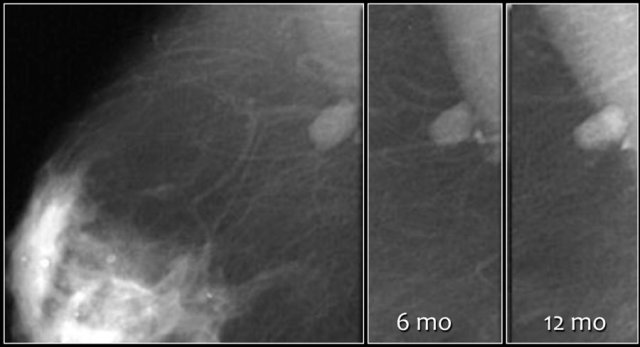

Here a non-palpable sharply defined mass with a group of punctate calcifications.

The mass was categorized as BI-RADS 3.

Continue with follow up images.

- The initial short-term follow-up of a BI-RADS 3 lesion is a unilateral mammogram at 6 months, then a bilateral follow-up examination at 12 months. Assuming stability perform a follow-up after one year and optionally after another year.

- If the findings shows no change in the follow up the final assessment is changed to BI-RADS 2 (benign) and no further follow up is needed.

Follow-up at 6, 12 and 24 months showed no change and the final assessment was changed into a Category 2.

Nevertheless the patient and the clinician preferred removal, because the radiologist was not able to present a clear differential diagnosis.

So add the following sentence in your report:

- BI-RADS 2 (benign finding).

- Instead of stopping the follow-up, tissue diagnosis will be performed, due to patient and referring clinician concern.

PA: benign vascular malformation.